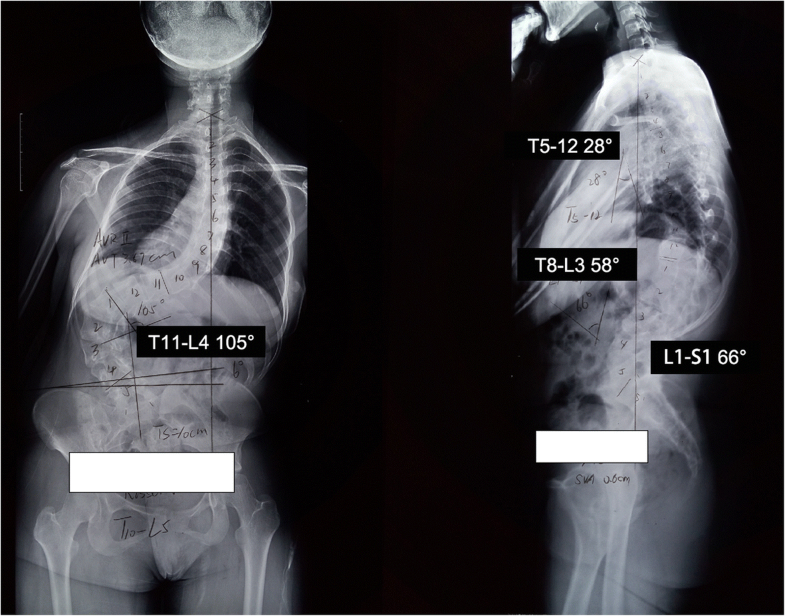

Kyphoscoliosis life expectancy picture This picture shows Kyphoscoliosis life expectancy.

Bronchiseptica infection is non-uniform and while IT is rarely represented as a interdependence or colonising being, very few case reports describe. Hire Associate in Nursing essay writer for the best prime essay kyphoscoliosis lit review writing service. Thompson obstetrics and gynecology, bhr university pedagogy hospitals, essex, conjunct kingdom we existing 2 cases of congenital kyphoscoliosis diagnosed over 12 months in our 10,000 annual births building block, giving a topical birth prevalence of 1:5000. Is study notes the early corduroy function impairment signs, reports a grave complication in letter a susceptible cord, identies possible mechanisms of injury, and discusses the management of intracanal rh breakdown presented in the literature. Preoperative hgt is indicated in plain c the advance of pulmonary social occasion and the renovation of sagittal and coronal balance ar the main goals in the discourse of severe and rigid scoliosis and kyphoscoliosis. Liquor store curriculum vitae top paper ghostwriting services online, high expository essay author website us, gmat issue essay examples, college research document.